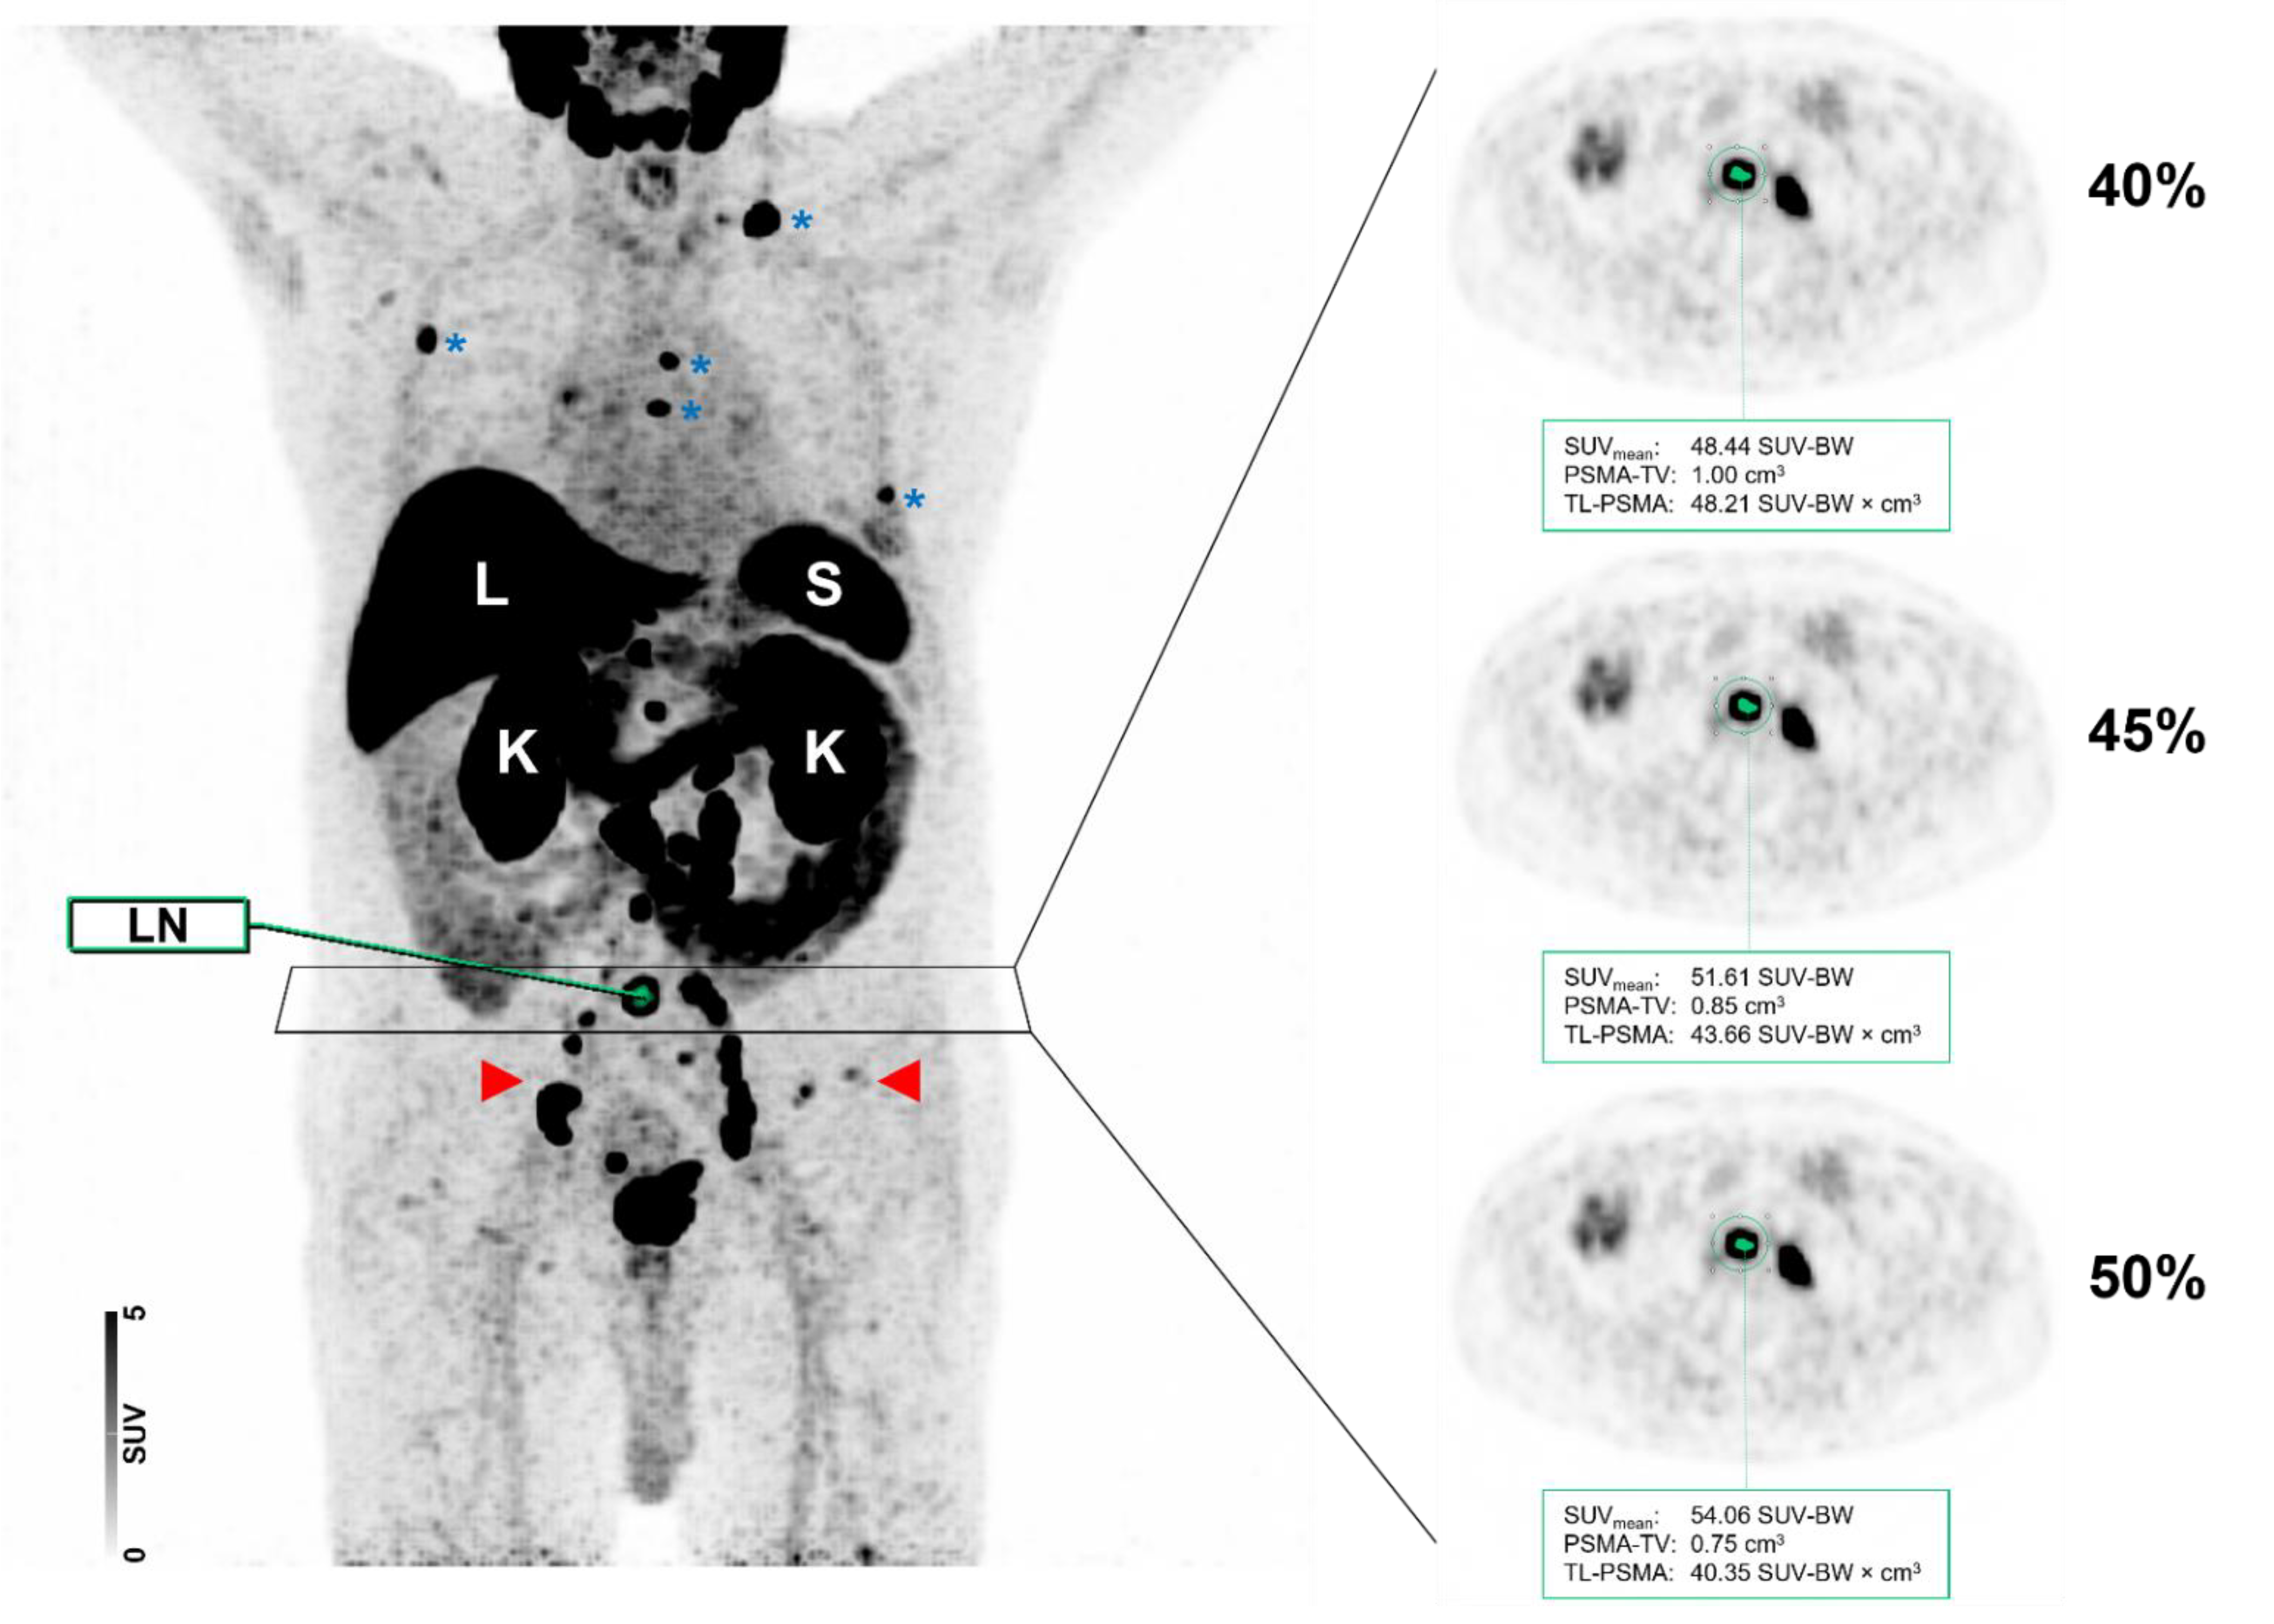

Figure 6 displays a case of lymph node and bone involvement with different MIT, demonstrating no significant differences in the segmentation of a lymph node metastasis attributable to PC.

Figure 6.

Maximum intensity projection (MIP) and axial positron emission tomography (PET) images of the same patient with different intensity thresholds (40 vs. 45 vs. 50%). Normal organ uptake in the liver (L), spleen (S), and kidneys (K) are indicated. The patient showed a relatively high tumor burden with multiple metastases involving both lymph nodes (red arrows) and the skeleton (blue asterisks). As shown for a PSMA-RADS-5 classified common iliac lymph node (LN), the segmentation did not differ visually when different maximum intensity thresholds of 40, 45, or 50% were applied.